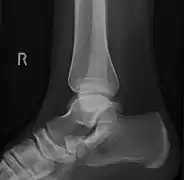

![]() X-ray of the foot showing an accessory navicular bone | |

An accessory navicular bone is an accessory bone of the foot that occasionally develops abnormally in front of the ankle towards the inside of the foot. This bone may be present in approximately 2-21% of the general population and is usually asymptomatic.[1][2][3] When it is symptomatic, surgery may be necessary.

To diagnose accessory navicular syndrome, the foot and ankle surgeon will ask about symptoms and examine the foot, looking for skin irritation or swelling. The doctor may press on the bony prominence to assess the area for discomfort. Foot structure, muscle strength, joint motion and the way the patient walks may also be evaluated. X-rays are usually ordered to confirm the diagnosis. If there is ongoing pain or inflammation, an MRI or other advanced imaging tests may be used to further evaluate the condition.[5]